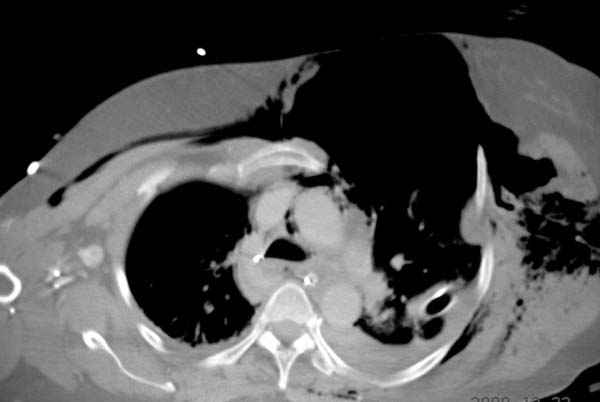

К нам поступила больная 56 лет после автоаварии в бессознательном состоянии, которая срочно заинтубирована в приемном отделении и сделаны необходимые исследования. Данные КТ и рентген показали перелом дистального бедра и Dissociation upper extremity - закрытый отрыв левой верхней конечности на уровне грудинно-ключичного сочленения и множественные переломы ребер.

На поверхности грудной клетки из-за полного разрыва грудной мышцы под кожей заметно биение сердца и след от ремня безопасности. Грудная клетка расширена из-за смещения верхней конечности вверх и латерально. Признаков васкулярного повреждения нет, и из-за отсутствия сознания не смогли определить наличия повреждения нервов.

После кожного разреза обнаружили полный разрыв грудной мышцы и повреждение перикард от уровня второго до восьмого ребер. Хирург находился с нами и после нашей работы зафиксировал повреждение перикарда и разрыв грудной мышцы.